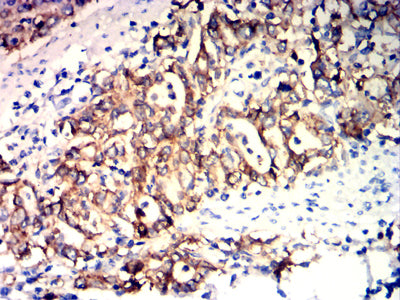

Immunohistochemical analysis of paraffin-embedded human lung cancer tissues using EPCAM mouse mAb with DAB staining.

Immunohistochemical analysis of paraffin-embedded human stomach cancer tissues using EPCAM mouse mAb with DAB staining.